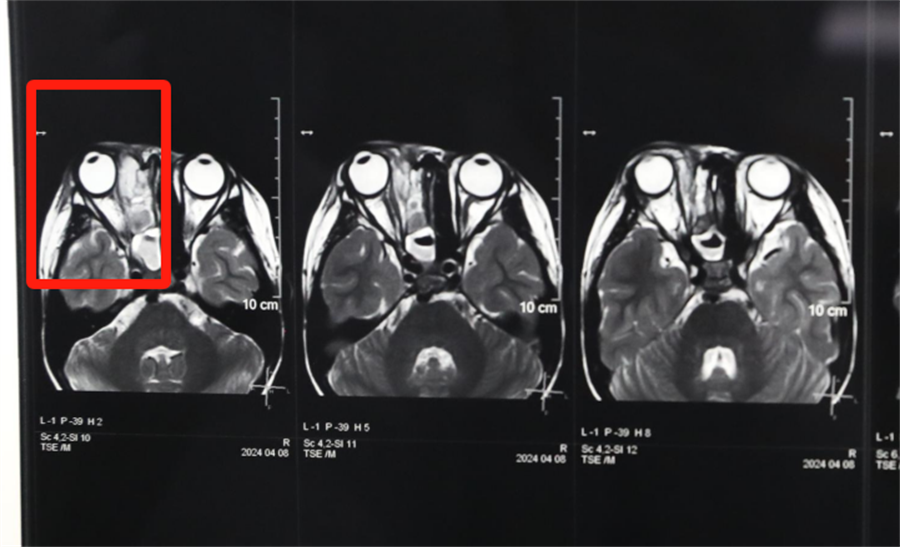

经眼科、耳鼻喉科联合会诊,医生发现孩子是因为患了急性鼻窦炎,导致右眼急性细菌感染,确诊为“右侧眶蜂窝织炎、眶内脓肿”。考虑到此病进展较快,可能导致视力下降甚至失明,耳鼻喉科立即将患儿收治入院。静脉输液、对症支持治疗、密切监测视力变化,一切有条不紊。入院第2天,孩子自觉右眼视力下降明显,眼科紧急会诊发现,其右眼视力从患病前的1.0下降到0.4。

北京儿童医院常驻专家、蜜桃视频 副院长杨小健决定立即手术治疗引流眶内脓液,并组织多学科联合会诊。考虑到患儿年龄较小,杨小健副院长决定采取内镜经鼻腔手术引流脓液,这种手术方式创伤小、恢复快、效果确切,而且避免了外切口瘢痕,不需要反复进行局部消毒换药。但是孩子鼻腔解剖结构本身就狭窄,而且处于急性感染期,术中出血风险较大,手术难度较高,对麻醉技术也有着很高的要求。

最终,杨小健副院长熟练地将手术器械通过小小的鼻孔,伸入到曾被公认为“手术禁区”的眶鼻交界区。一个多小时后,她成功地将眼眶脓肿充分引流出来。术后,医院多学科团队密切观察患儿病情变化,每日查房讨论并及时调整治疗方案。最终,通过全体医护人员的共同努力,患儿术后第3天右眼斜视就消失了,视力也恢复到了1.0。术后5天,患儿高高兴兴地出院了。